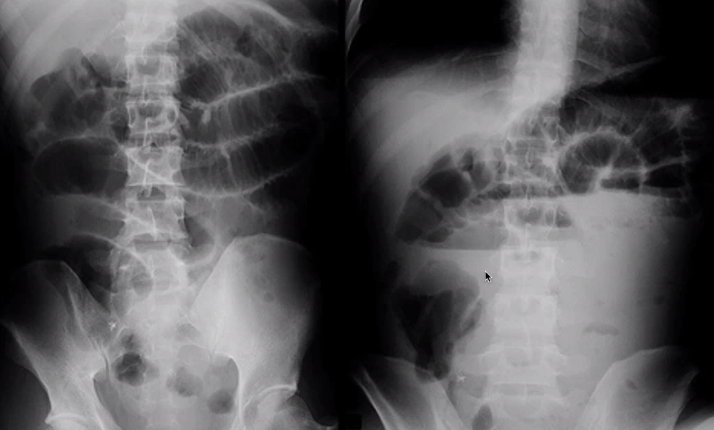

what is the pathology here?

type of imaging modality

SBO obstruction

AXR